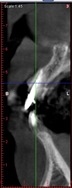

立體斷層掃描。

手術後,植體順利的植入預設的位置

當天拔牙,且立即植牙。

手術後,植體順利的植入預設的位置。